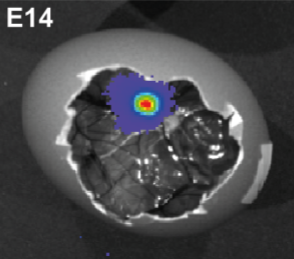

We are experts in chorioallantoic membrane (CAM) xenograft models of cancer cells, including world-leading patient-derived xenografts (PDX) to translate therapeutic approaches and are uniquely adapting multiple preclinical imaging modalities for these models.

- Generating CAM xenografts (cell lines, co-cultures or patient-derived tissues) for cancer biology studies and drug efficacy testing

- Angiogenesis studies